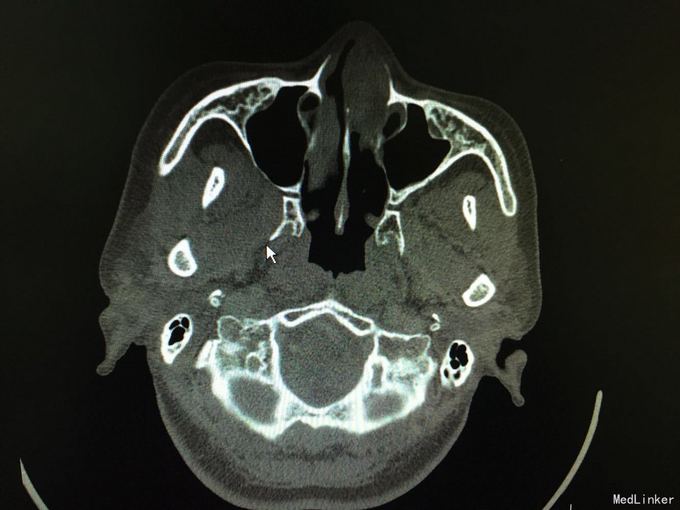

以“间断性左鼻腔出血5月,加重1月”为主诉入院。5月前劳累后出现左鼻腔出血,量中等,可自止,无明显鼻塞、流涕、鼻腔异味,自行口服药物后异味消失(具体药物不详),未正规治疗,1月来左侧鼻腔间断性出血,约3-5天1次,量少,偶浓涕、头晕,无明显鼻痒、喷嚏症状。

查体:双侧鼻腔黏膜充血,左侧总鼻道可见肿物,表面糜烂,质硬,触之易出血,左侧中鼻道窥不及,右侧鼻腔各鼻道未见明显新生物,无活动性出血,鼻中隔偏曲。 增强CT显示肿物内强化明显。

诊断:1.鼻腔血管瘤(左) 2.鼻出血(左) 3.结构性鼻炎 介入手术后3天行低温等离子左鼻腔肿瘤切除术